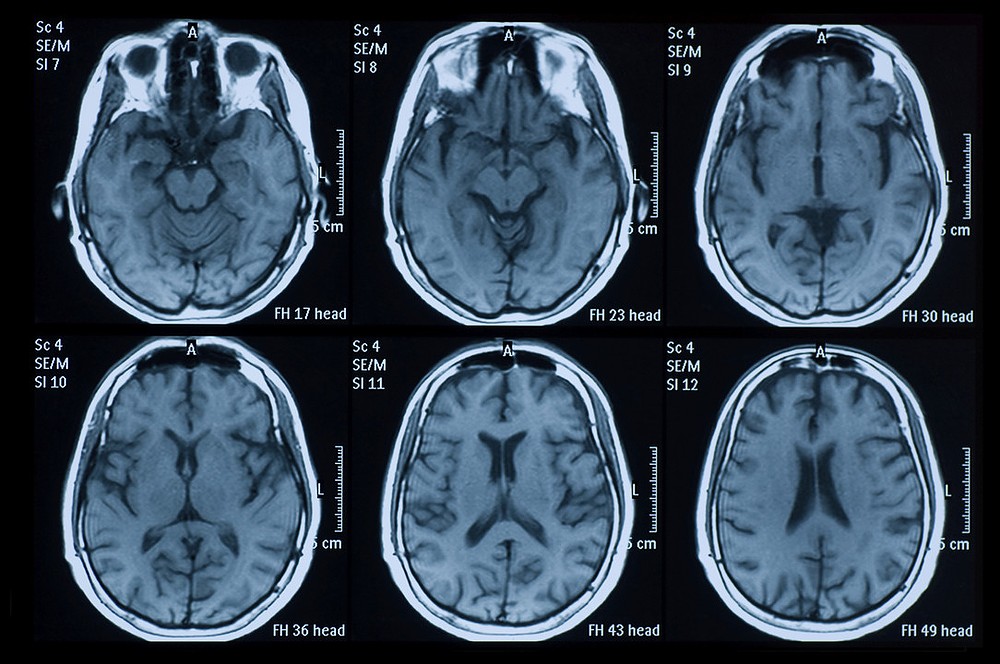

Pro tuto neurodegenerativní nemoc je typické zpomalení pohybů, třes, ztuhlost svalů či poruchy rovnováhy a později vůlí neovlivnitelný pohybový neklid. „Nemoc způsobuje odumírání mozkových buněk, které produkují především dopamin.

Člověk tak postupně ztrácí kontrolu nad svými pohyby. Současná medicína neumí Parkinsonovu nemoc vyléčit, ale zásadně mírní příznaky,“ řekl prof.

MUDr. Robert Jech, Ph.D., vedoucí lékař centra pro intervenční léčbu motorických poruch Neurologické kliniky 1. lékařské fakulty UK a VFN v Praze.